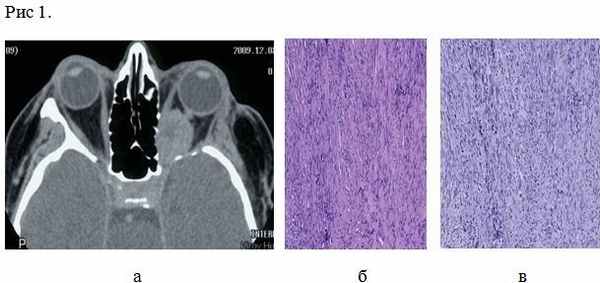

В 2005 г., спустя 17 лет с момента начала заболевания, стало вновь снижаться зрение на левый глаз, и пациентка впервые обратилась в НИИ нейрохирургии им. Н.Н. Бурденко. При обследовании выявлены зрительные расстройства: острота зрения слева — светоощущение; грубый парез третьего нерва слева (птоз, глазодвигательные нарушения). При КТ — опухоль левой орбиты. Произведено удаление опухоли, которая располагалась в верхушке орбиты и распространялась на верхнюю глазничную щель и зрительный канал. Гистологический диагноз (04.08.05): нейрофиброма. После операции: репозиция глазного яблока при сохраняющемся птозе верхнего века и частичном регрессе глазодвигательных расстройств. В августе 2008 г. вновь госпитализирована в НИИ нейрохирургии в связи с прогрессированием заболевания, развитием клиники объемного поражения левой орбиты в виде экзофтальма 5 мм и нарастания зрительных расстройств до амавроза. Рентгенологически определялась опухоль в области верхушки левой орбиты. Произведено удаление опухоли. На операции в области верхушки глазницы под надкостницей определялась светло-желтого цвета, плотной консистенции опухоль. Опухоль не инфильтрировала окружающие структуры и была удалена узлом. При контрольной КТ с контрастным усилением остатков опухоли не выявлено. Гистологический диагноз: нейрофиброма, индекс лечения Ki-67 составил 5% (см. рисунок, I). Рисунок 1. Нейрофиброма 2008 г. ( I), MPNST — 2010 г. (II) и 2012 г. (III). а — КТ; б, в — гистологические препараты; окраска гематоксилином и эозином; в — Ki-67: 50% (I), 10% (II), 30% (III). После операции экзофтальм регрессировал, наросли глазодвигательные нарушения.

Гистологическое заключение: нейрофиброма со злокачественной трансформацией в злокачественную опухоль оболочек периферического нерва (MPNST). Индекс лечения Ki-67 равен 10% (см. рисунок, II). При контрольной КТ остатков опухоли не выявлено. Клинически после операции отмечался регресс экзофтальма; сохранялись офтальмоплегия, амавроз, птоз верхнего века. По месту жительства в июле 2010 г. проведена лучевая терапия в СОД 63 Гр. С осени 2012 г. вновь стал нарастать экзофтальм слева, появились боли в левой глазнице. При контрольной КТ (ноябрь 2011 г.) выявлен рецидив опухоли в левой глазнице. Помимо этого развился левосторонний кератоувеит с угрозой перфорации глазного яблока. При УЗИ выявлено образование в орбите, вплотную подходящее к заднему полюсу глаза. Учитывая наличие амавроза, офтальмоплегии, трофических расстройств, а также высокий риск перфорации глазного яблока, было принято решение об удалении опухоли вместе с глазным яблоком, операция выполнена в НИИ нейрохирургии 14.02.12 г. При контрольной КТ остатков опухоли не выявлено.

Гистологическое заключение — злокачественная опухоль оболочек периферического нерва (MPNST). Индекс лечения Ki-67 равен 30% (см. рисунок, III). Проведена лучевая терапия в СОД 66 Гр. На момент написания статьи клинико-рентгенологических признаков рецидива нет.

Пациентка К., 65 лет. Из анамнеза известно, что в 1988 г. отметила снижение зрения слева, двоение предметов перед глазами. Обследована в МНИИ ГБ им. Гельмгольца, выявлено снижение остроты зрения на левый глаз до 0,7; при КТ выявлена опухоль левой орбиты, произведено оперативное вмешательство - удаление опухоли. Гистологический диагноз (сентябрь 1988 г.): «нехромафинная параганглиома». После операции зрение восстановилось, глазодвигательные расстройства регрессировали полностью. Около 5 лет больная наблюдалась в МНИИ ГБ им. Гельмгольца, состояние оставалось стабильным, рентгенологически признаков рецидива не определялось. В 1990 г. пациентке проведено комбинированное лечение (хирургическое удаление опухоли с последующей радиотерапией) опухоли кожи (базалиомы) в области fossa canina слева. В 2005 г., спустя 17 лет с момента начала заболевания, стало вновь снижаться зрение на левый глаз, и пациентка впервые обратилась в НИИ нейрохирургии им. Н.Н. Бурденко. При обследовании выявлены зрительные расстройства: OS – светоощущение; грубый парез III нерва слева (птоз, глазодвигательные нарушения). При КТ – рецидив опухоли левой орбиты. Произведено повторное удаление опухоли, которая располагалась в верхушке орбиты и распространялась на верхнюю глазничную щель и зрительный канал. Гистологический диагноз (04.08.2005): нейрофиброма. После операции: репозиция глазного яблока при сохраняющемся птозе и частичном регрессе глазодвигательных расстройств. В августе 2008 г. вновь госпитализирована в ИНХ в связи с прогрессированием заболевания, развитием клиники объемного поражения левой орбиты в виде экзофтальма 5 мм и нарастания зрительных расстройств до амавроза. Рентгенологически определялась опухоль в области верхушки левой орбиты. Произведено удаление опухоли. На операции в области верхушки глазницы под надкостницей определялась светло-желтого цвета, плотной консистенции опухоль. Опухоль не инфильтрировала окружающие структуры и была удалена узлом. При контрольной КТ с контрастным усилением остатков опухоли не выялено. Гистологический диагноз: нейрофиброма. Ki-67 – 5% (Рис. 1). После операции экзофтальм регрессировал, наросли глазодвигательные нарушения.

Гистологическое заключение: нейрофиброма со злокачественной трансформацией в злокачественную опухоль оболочек периферических нервов (MPNST). Ki-67 10% (Рис. 2). При контрольной КТ данных за остатки опухоли выявлено не было. Клинически после операции отмечался регресс экзофтальма; сохранились офтальмоплегия, амавроз, птоз. По месту жительства в июле 2010 г. проведена радиотерапия в СОД 63 Гр. С осени 2012 г. вновь стал нарастать экзофтальм слева, появились боли в левой глазнице. При контрольной КТ головного мозга (ноябрь 2011г) определяется рецидив опухоли в левой глазнице. Помимо этого развился левосторонний кератоувеит с угрозой перфорации глазного яблока. При УЗИ выявлено образование в орбите, вплотную подходящее к заднему полюсу глаза. В феврале 2012 г. госпитализирована в ИНХ для хирургического лечения. Учитывает наличие амавроза, офтальмоплегии, трофических расстройств, а также высокий риск перфорации глазного яблока, было принято решение об удалении опухоли вместе с глазным яблоком. 14.02.2012 г. произведена операция. При контрольной КТ головного мозга и глазницы данных за остатки опухоли не выявлено.

Гистологическое заключение - злокачественная опухоль периферических нервов (MPNST). Ki-67 – 30% (Рис. 3). Проведена ЛТ в СОД 66 Гр. На момент написания статьи клинико-рентгенологических признаков рецидива нет.